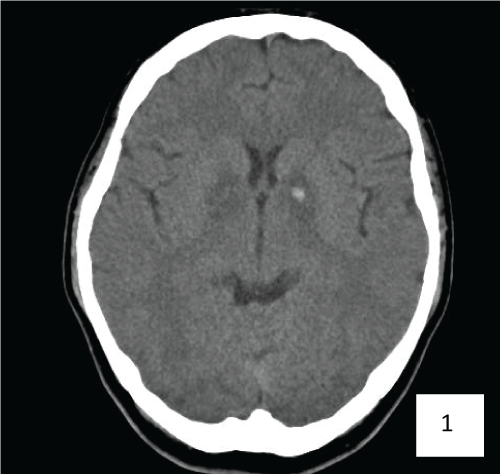

A 41-year-old gentleman attempted suicide by burning charcoal in an enclosed room. He was found unconscious and was intubated for poor Glasgow Coma Scale (GCS). He was successfully extubated and transferred to our hospital on day 6. Initial physical examination showed no neurological deficits with normal scoring of Mini-Mental State Examination (MMSE) and Montreal Cognitive Assessment (MOCA). Computerized Tomography (CT scan) of the brain was done on day 8 (Figure 1). Magnetic Resonance Imaging (MRI) of brain done on day 10 was shown in Figure 2A and Figure 2B. He had major depression and was transferred to the care of psychiatrist. Initial neuropsychological assessment showed subtle deficits in learning, retrieval of information and verbal fluency.

Figure 1: CT brain on day 8: symmetrical hypodensity at the globus pallidus with a small focus of acute hemorrhage on the left.